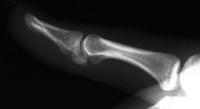

Case 3. 21 year old woman with pain developing in a congenitally angulated thumb.

Radiographs show a juxtaarticular ossification with  subchondral cyst formation of the bone interface with the lateral phalangeal head and lateral angulation of the proximal phalanx articular surface.